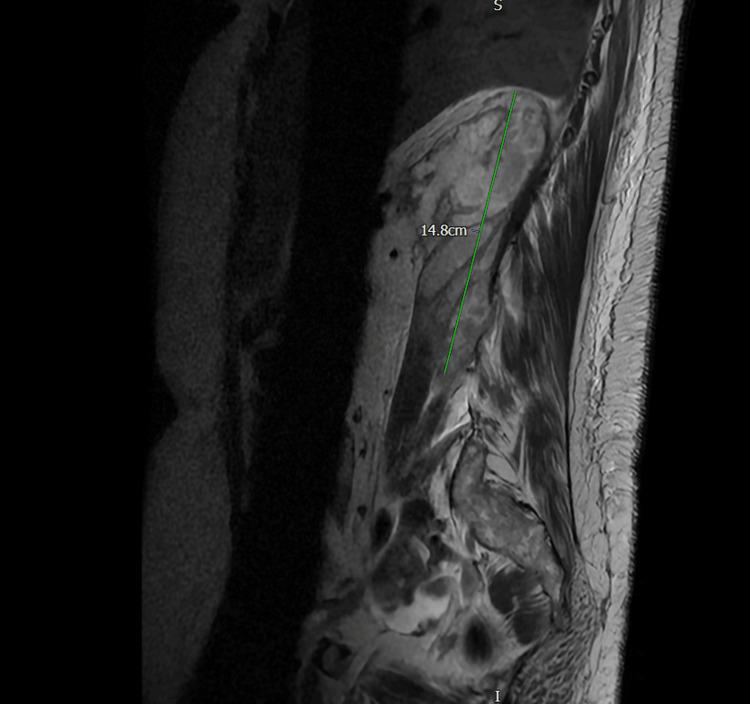

Iliopsoas abscess is a rare infection that presents with a triad of fever, back pain, and hip pain. However, due to the anatomical proximity of the psoas muscle to various structures, an abscess in this region can manifest with nonspecific symptoms, leading to potential misdiagnosis and delayed diagnosis, which can be fatal. We report a case of a 54-year-old female who presented to the emergency department with right-sided flank pain and symptoms resembling lower motor neuron disorder. Initial investigations were inconclusive until an MRI revealed a large retroperitoneal collection in the right perinephric space and iliopsoas muscle, likely of urological origin, with no spinal abnormalities. Intravenous gentamicin was initiated. A subsequent contrast-enhanced CT scan of the abdomen and pelvis confirmed a right posterior perinephric collection. Ultrasound-guided drainage was performed, and a pigtail catheter was placed in situ for continuous drainage along with targeted antibiotics based on culture and sensitivity.

髂腰肌脓肿是一种罕见的感染性疾病,表现为发热、背痛和髋部疼痛三联征。然而,由于腰大肌与各种结构在解剖位置上相邻,该区域的脓肿可能表现为非特异性症状,导致潜在的误诊和诊断延迟,这可能是致命的。我们报告一例54岁女性,因右侧胁腹疼痛及类似下运动神经元疾病的症状就诊于急诊科。最初的检查结果不明确,直到磁共振成像(MRI)显示右肾周间隙和髂腰肌有一个大的腹膜后积液,可能源于泌尿系统,且无脊柱异常。开始静脉注射庆大霉素。随后的腹部和盆腔增强CT扫描证实右肾后有积液。进行了超声引导下引流,并置入一根猪尾导管进行持续引流,同时根据培养和药敏结果使用针对性抗生素。